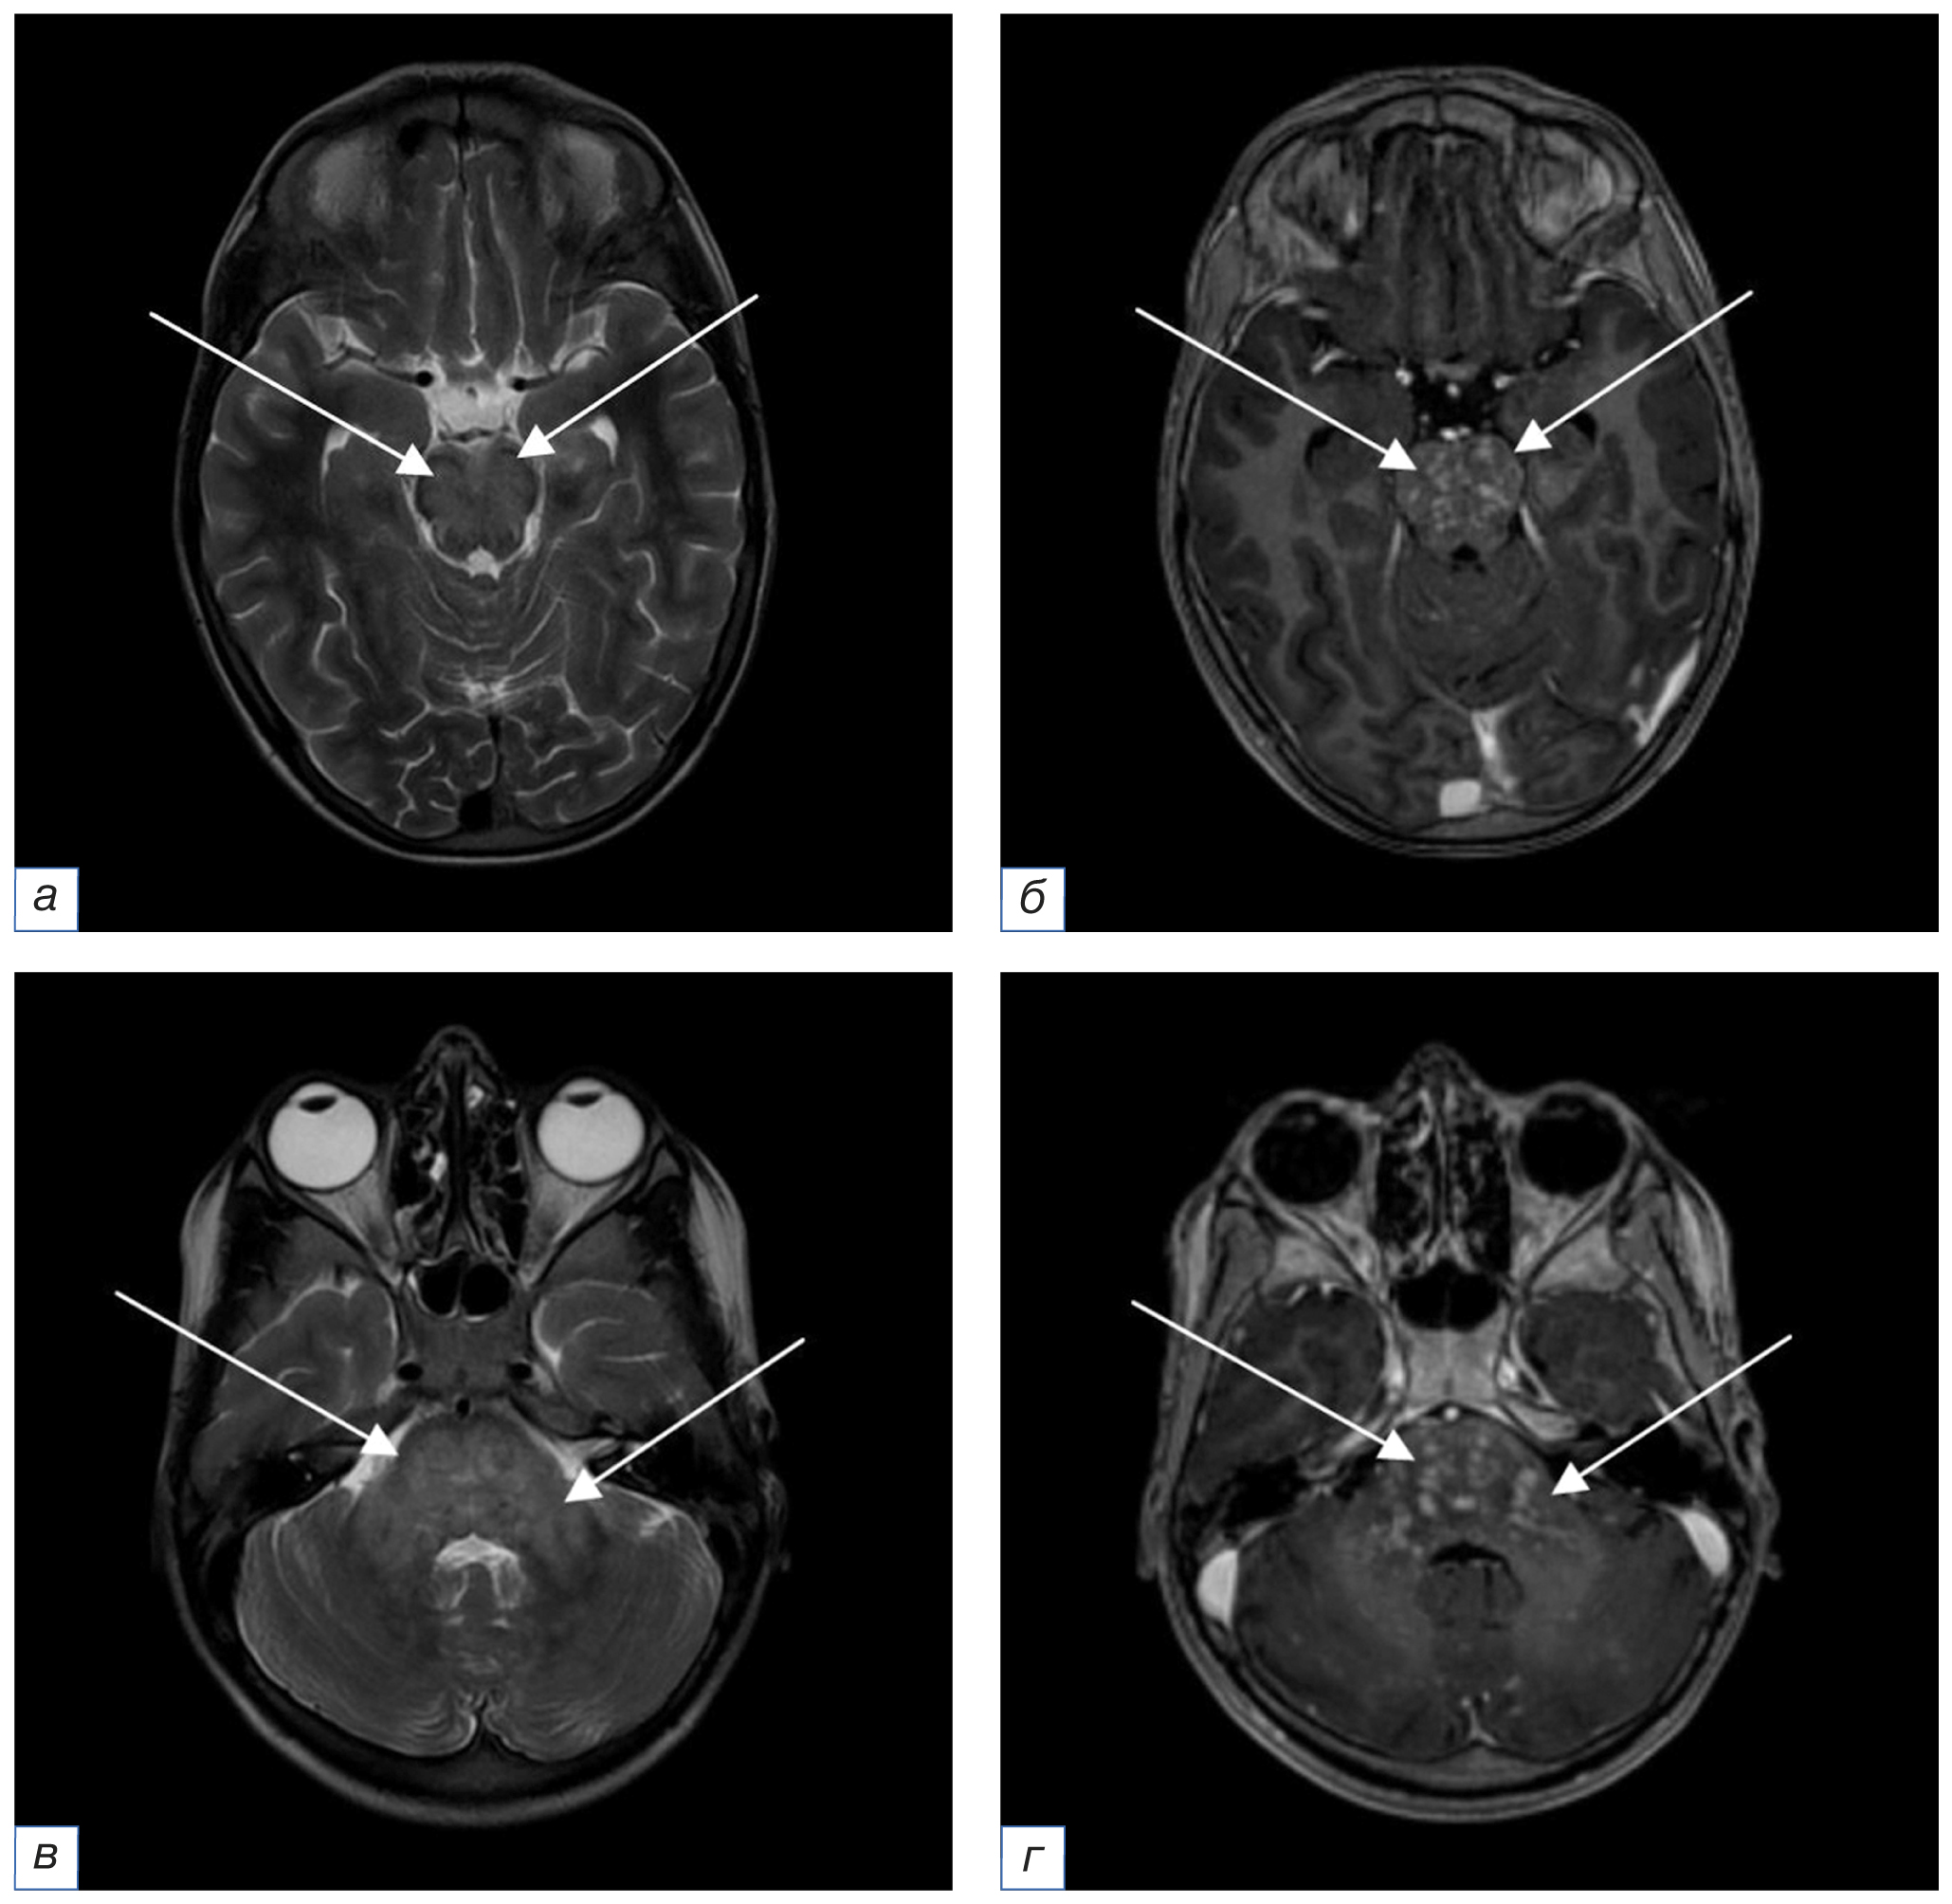

16.08.2021. При проведении повторной МРТ с внутривенным контрастным усилением (рис. 2) сохранялись ранее выявленные очаги прежних размеров и структуры. На фоне контрастирования долженствующего накопления контрастного вещества очагами не определялось, вероятно, за счет ранее проведенного курса пульс-терапии.

Рис. 2. Повторное, после 5 дней пульс-терапии, МРТ головного мозга в аксиальной плоскости с внутривенным контрастным усилением от 16.08.2021 (a, в — режим Т2-ВИ; б, г — режим FLAIR; д, е — режим Т1-ВИ до и после введения контрастного вещества соответственно): по сравнению с данными МРТ от 12.03.2020 сохраняются мелкие очаги измененного МР-сигнала прежней локализации, структуры и размеров (стрелки). На фоне контрастного усиления долженствующего накопления контрастного вещества не визуализируется, вероятно, вследствие кратковременного курса пульс-терапии (стрелки). / Fig. 2. Follow-up (after 5 days of pulse therapy) MRI of the brain in the axial plane of August 16, 2021 with intravenous contrast enhancement (a, в — T2-weighted image; б, г — FLAIR; д, е — T1-weighted image before and after contrast enhancement respectively): compared with the MRI data of March 12, 2020, small foci of the altered MR signal with the same localization, structure and size remain (arrows). A short-term pulse therapy course doesn’t result in strong contrast enhancement (arrows).

В декабре 2021 г. ребенок перенес фокальный эпилептический приступ с версией глаз. Отмечались кратковременная остановка дыхания, выраженные головные боли, тошнота с рвотой. Компьютерная томография (КТ) головного мозга, органов грудной клетки, органов брюшной полости и забрюшинного пространства патологических изменений не выявила. Результаты анализов крови на антитела и методом полимеразной цепной реакции позволили исключить основные инфекционные агенты. Анализ спинномозговой жидкости от 27.12.2021 выявил минимально повышенное количество белка (0,477 г/л), при посеве этиологически значимой микрофлоры не обнаружено. На основании проведенных исследований выставлен предварительный диагноз «Рассеянный склероз», несмотря на то, что диагностические критерии не были соблюдены. Лечение состояло из пульс-терапии метилпреднизолоном (15 мг/кг в сутки в течение 5 дней). Наблюдалась положительная динамика, в результате ребенок был выписан домой в удовлетворительном состоянии. На МР-томограммах с внутривенным контрастным усилением от 10.01.2022 сохранялись очаги прежней локализации и структуры с интенсивным накоплением контрастного вещества (рис. 3).

Рис. 3. МРТ головного мозга в аксиальной плоскости от 10.01.2022 с внутривенным контрастным усилением (a, в — режим Т2-ВИ; б, г — режим Т1-ВИ после введения контрастного вещества): по сравнению с данными МРТ от 16.08.2021 сохраняются мелкие очаги измененного МР-сигнала прежней локализации, структуры и размеров (стрелки). На фоне контрастного усиления визуализируется интенсивное накопление контрастного вещества (стрелки). / Fig. 3. MRI of the brain in the axial plane of January 10, 2022 with intravenous contrast enhancement (a, в — T2-weighted image; б, г — T1-weighted image after contrast enhancement): compared with the MRI data of August 16, 2021, small foci of the altered MR signal with the same localization, structure and size remain (arrows). Strong positive contrast enhancement is visualized (arrows).